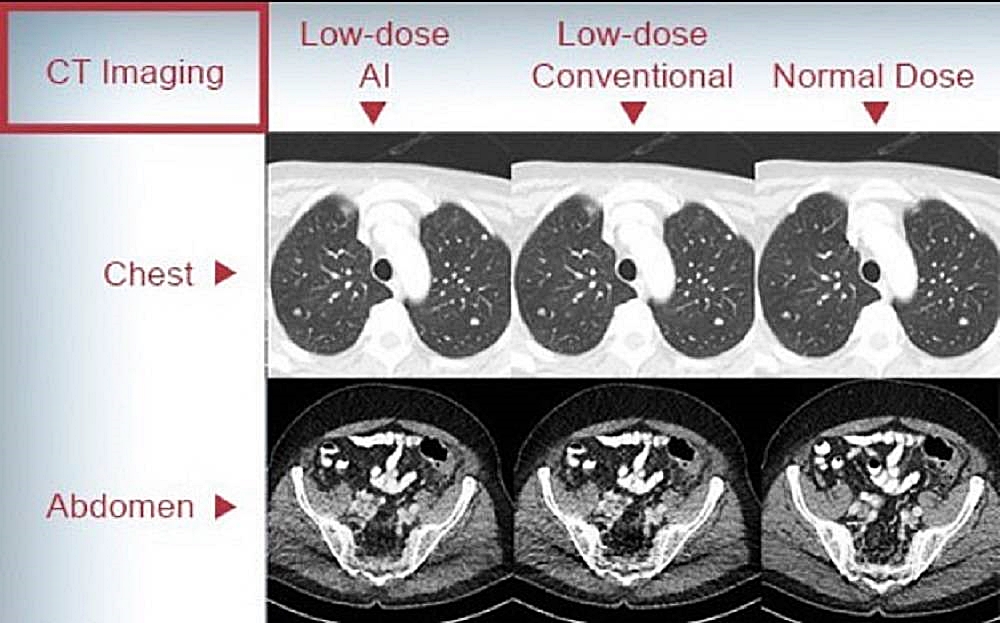

ในส่วนของมะเร็งปอดในกลุ่มผู้ไม่สูบบุหรี่นั้น จากข้อมูลที่ควรรู้ประมาณ 40-60 % ของมะเร็งปอดเกิดในผู้ที่ไม่เคยสูบบุหรี่ซึ่งมักเกิดจากการได้รับควันบุหรี่มือสอง, การสัมผัสก๊าซเรดอน, การสัมผัสสารพิษจากงานอาชีพ (เช่น แร่ใยหิน ควันดีเซล), มลพิษทางอากาศ หรือ ครัวเรือน, ประวัติครอบครัวเป็นมะเร็งปอด, การกลายพันธุ์ทางพันธุกรรม (เช่น EGFR, ALK) โดยมะเร็งปอดในผู้ไม่สูบบุหรี่มักเป็นชนิด อะดีโนคาร์ซิโนมา (Adenocarcinoma) ซึ่งมากกว่า 60-70% มักถูกวินิจฉัยในระยะที่ลุกลามแล้ว เพราะไม่มีการตรวจคัดกรองที่เหมาะสมโดยปัจจุบันยังไม่มีแนวทางการตรวจคัดกรองสำหรับผู้ไม่สูบบุหรี่ระดับชาติหรือสากล ที่ แนะนำให้ตรวจ LDCT เป็นการตรวจเอกซเรย์คอมพิวเตอร์บริเวณทรวงอกด้วยปริมาณรังสีที่ต่ำมาก ใช้เพื่อคัดกรองมะเร็งปอดในระยะเริ่มต้นในผู้ที่ไม่เคยสูบบุหรี่ทั่วไป โดยผลจากการตรวจ LDCT พบว่า 1. อัตราความเสี่ยงต่อประโยชน์ยังไม่ชัดเจน (ตรวจพบผลลวงบ่อย, ได้รับรังสี) และ 2.ยังไม่มีหลักฐานชัดเจนว่าช่วยให้รอดชีวิตเพิ่มขึ้นในกลุ่มความเสี่ยงต่ำ

ส่วนข้อควรระวังและประเมินก่อนตรวจ LDCT นั้น แม้จะช่วยลดอัตราการเสียชีวิตจากมะเร็งปอดในกลุ่มเสี่ยงสูง แต่ก็มีข้อควรพิจารณา เช่น 1. ผลบวกลวง (False Positive) โดยอาจพบก้อนที่ไม่ใช่มะเร็ง ทำให้ต้องตรวจเพิ่มเติมหรือผ่าตัดโดยไม่จำเป็น 2.การได้รับรังสีซ้ำซ้อนและ 3.ความวิตกกังวลจากผลตรวจ โดยมีบางรายอาจมีข้อยกเว้นหรือกรณีพิเศษ อาจมีประโยชน์ต่อการคัดกรองความเสี่ยง ได้แก่ 1.ประวัติครอบครัวที่ชัดเจนว่าเคยเป็นมะเร็งปอด 2.การสัมผัสสารพิษจากสิ่งแวดล้อมหรือจากอาชีพอย่างมีนัยสำคัญและ 3.พันธุกรรมที่เสี่ยงต่อการเป็นมะเร็ง กรณีเหล่านี้ควรพูดคุยกับแพทย์ และพิจารณาอย่างรอบคอบร่วมกัน โดยมากจะอยู่ในบริบทของการวิจัยหรือติดตามเฝ้าระวังกลุ่มเสี่ยงสูง โดยปัจจุบันการใช้ฟิล์มเอกซเรย์ในการตรวจคัดกรองมะเร็งปอดหรือการเจาะเลือด ยังไม่ใช่วิธีมาตรฐานที่มีความแม่นยำอีกต่อไป ฉะนั้นใครที่มีความเสี่ยง อย่าลืมไปคัดกรองมะเร็งปอดโดยการทำ LDCT กันนะครับ